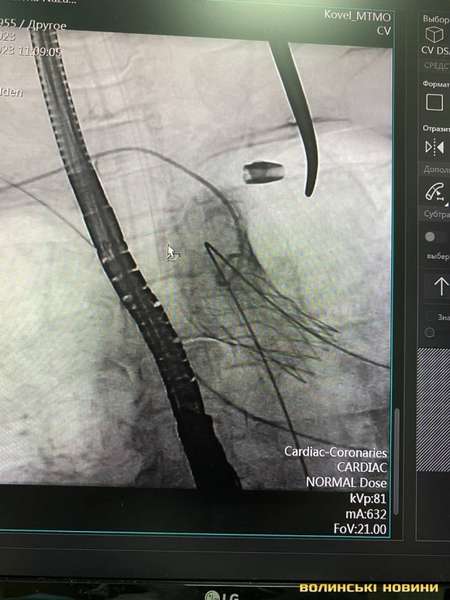

Лікарі Центру дитячої кардіології та кардіохірургії (м. Київ) спільно зі спеціалістами Ковельського МТМО виконали процедуру TAVI – транскатетерну заміну аортальна клапана.

Лікарі замінили аортальний клапан без зупинки серця через 3-х сантиметровий розріз. Тривалість операції на серці склала 2 години.

«Нашій пацієнтці 68 років, вона страждала від критичного стенозу аортального клапана – вади серця, при якій один із основних клапанів майже не відкривається. Але зараз вона в стабільному стані і тепер попереду в неї здорове та повноцінне життя», – розповів завідувач кардіохірургічного центру Володимир Танський.